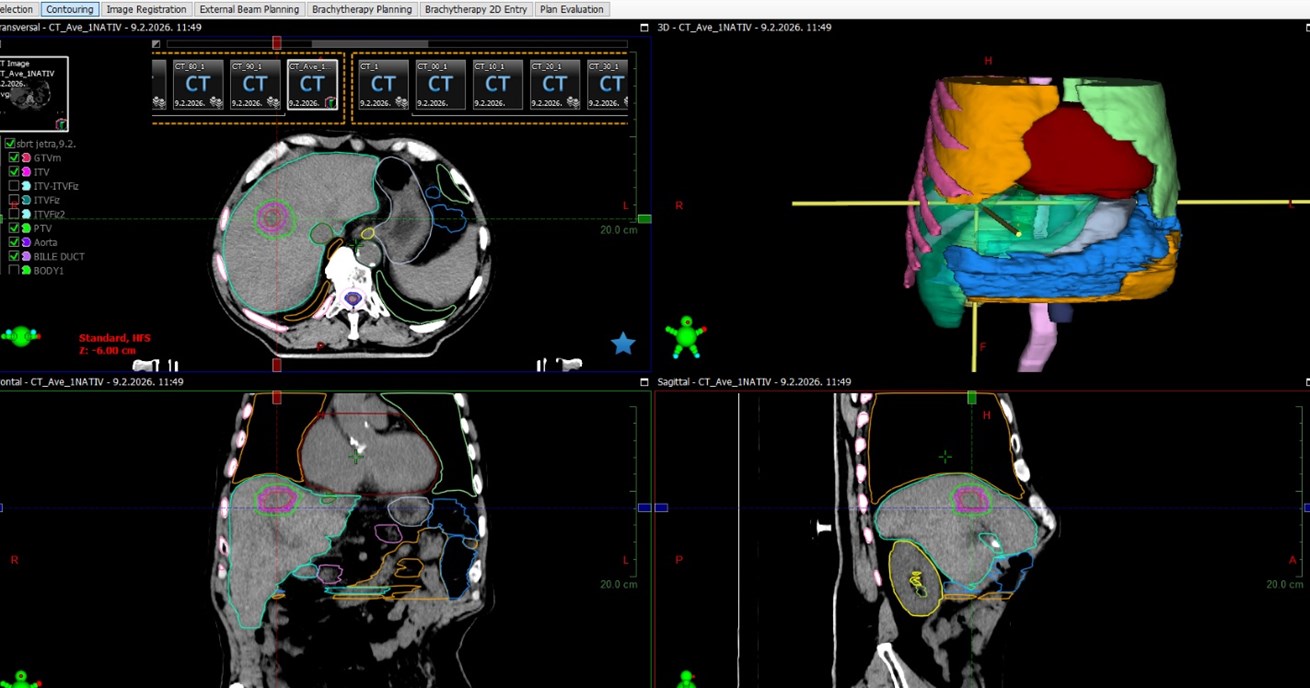

Klinika za tumore KBC-a Rijeka prva je u Hrvatskoj uvela stereotaksijsku radioterapiju jetre (SBRT), jednu od najnaprednijih i tehnički najzahtjevnijih metoda liječenja metastaza i primarnih tumora.

Ovime je postala prva ustanova u javnom zdravstvu koja provodi ovaj zahvat. Metoda predstavlja novi iskorak, jer nakon nedavne uspješne stereotaksije mozga i pluća, uvođenjem ovog – najkompleksnijeg SBRT zahvata, sada je u Rijeci moguće napraviti stereotaksiju na lezijama cijelog tijela.

Stereotaksijska radioterapija (SBRT) jetre danas predstavlja jednu od najnaprednijih i najpreciznijih metoda liječenja malignih promjena jetre (bilo metastaza  ili primarnog tumora jetre). SBRT jetre je tehnika kojom se u malom broju frakcija (najčešće 3–5) isporučuju visoke biološki učinkovite doze zračenja s milimetarskom preciznošću, uz strogu kontrolu položaja tumora, kompenzaciju pokreta uzrokovanih disanjem te uz maksimalnu zaštitu zdravog tkiva jetre.

Jetra je vitalni organ jer bez nje organizam ne može preživjeti. Obavlja više od 500 različitih funkcija koje su ključne za život, radi toga i njene respiratorne pomičnosti, SBRT jetre predstavlja najkompleksniji oblik stereotaktične radiokirurgije. Tijekom planiranja zračenja metastaze ili tumora jetre nužno je voditi brigu o funkciji jetre, te o preostalom zdravom parenhimu jetre koji će moći preuzeti sve potrebne funkcije.